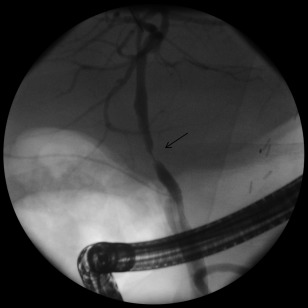

Figure 1.

Posttransplant biliary ASs on ERCP (arrow).